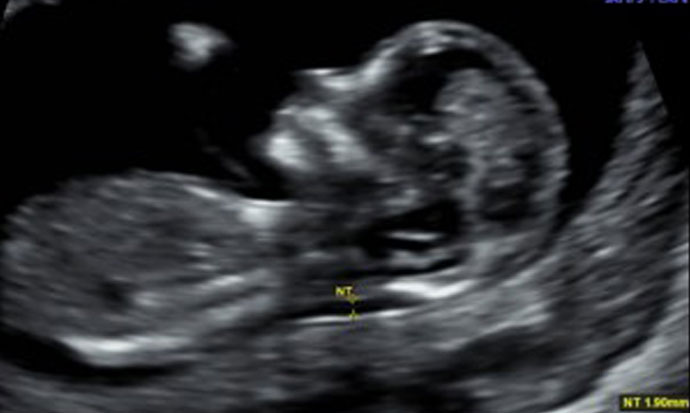

Pregnancy ultrasound scans at Bourn Hall Clinic for reassurance

Unborn babies can be seen in remarkable detail using 3D and 4D ultrasound scans.